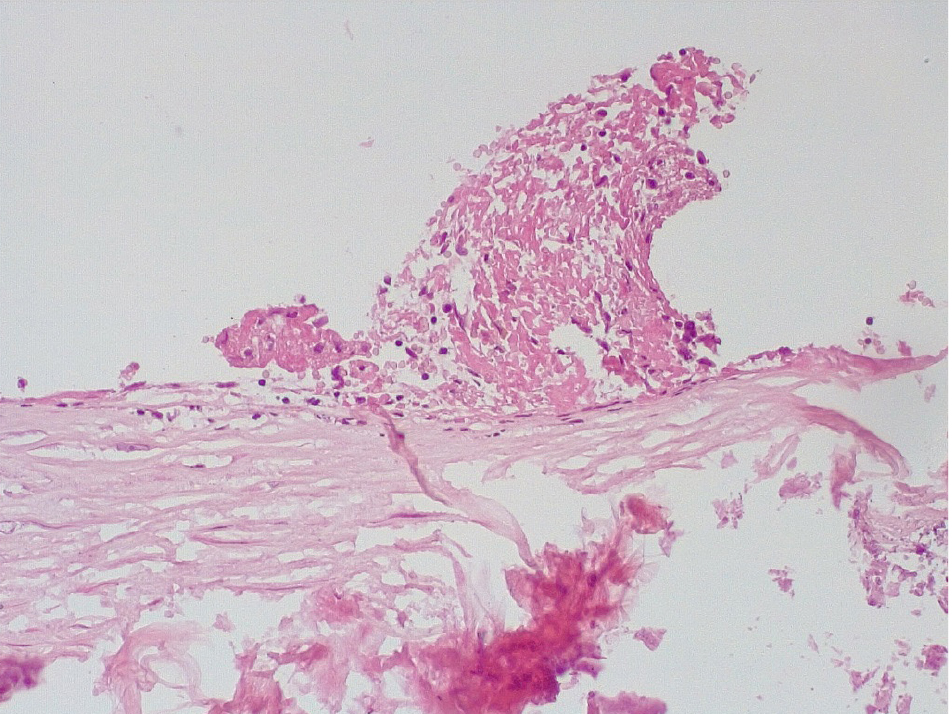

Позднее, спустя 3–7 суток после стентирования КА в просветах имелись пристеночные смешанные фибриново-лейкоцитарные тромбы, которые могли служить источником развития тромбоэмболических осложнений мелких дистальных ветвей коронарного кровотока и развитием острого инфаркта миокарда (рис. 4).

Маркер эндотелиальной дисфункции – фактор Виллебранда (ФВ) ярко экспрессировался в клетках эндотелия КА и субинтимально, что могло свидетельствовать о выраженной дисрегуляции коагуляционных свойств крови (рис. 5). В то же время экспрессия белка CD31 в указанные сроки после стентирования была слабовыраженной, что могло указывать на выраженные дистрофические изменения эндотелиальных клеток КА.